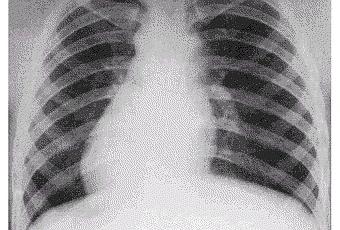

El término que da nombre a esta enfermedad, proveniente del latín, significa traducido al español “posición invertida de los órganos”.

Como su nombre lo indica, la enfermedad consiste en una colocación invertida de los órganos (en espejo).